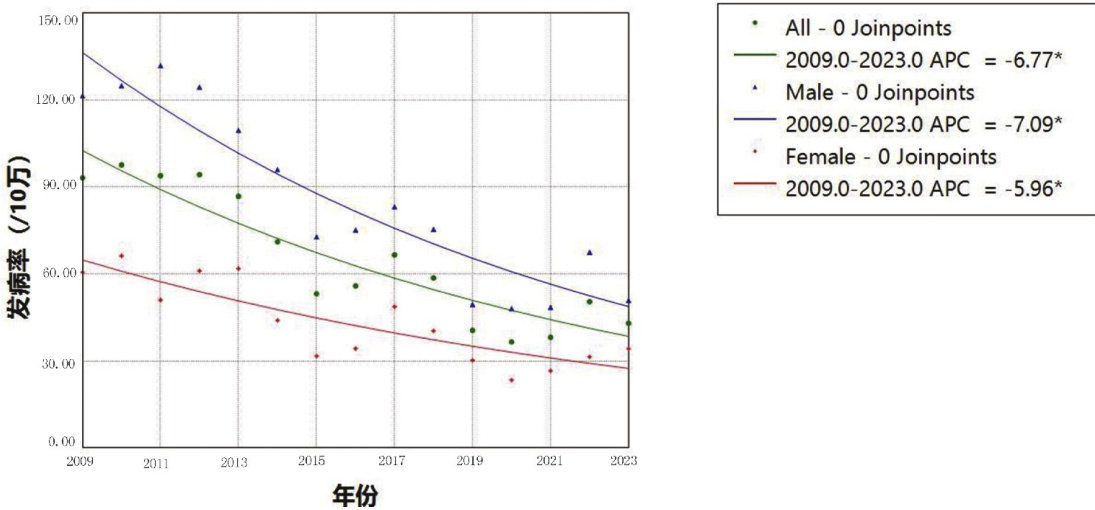

论著·临床研究 | 2009—2023年广西隆安县乙型肝炎流行病学特征与趋势分析

论著·临床研究 | 2009—2023年广西隆安县乙型肝炎流行病学特征与趋势分析